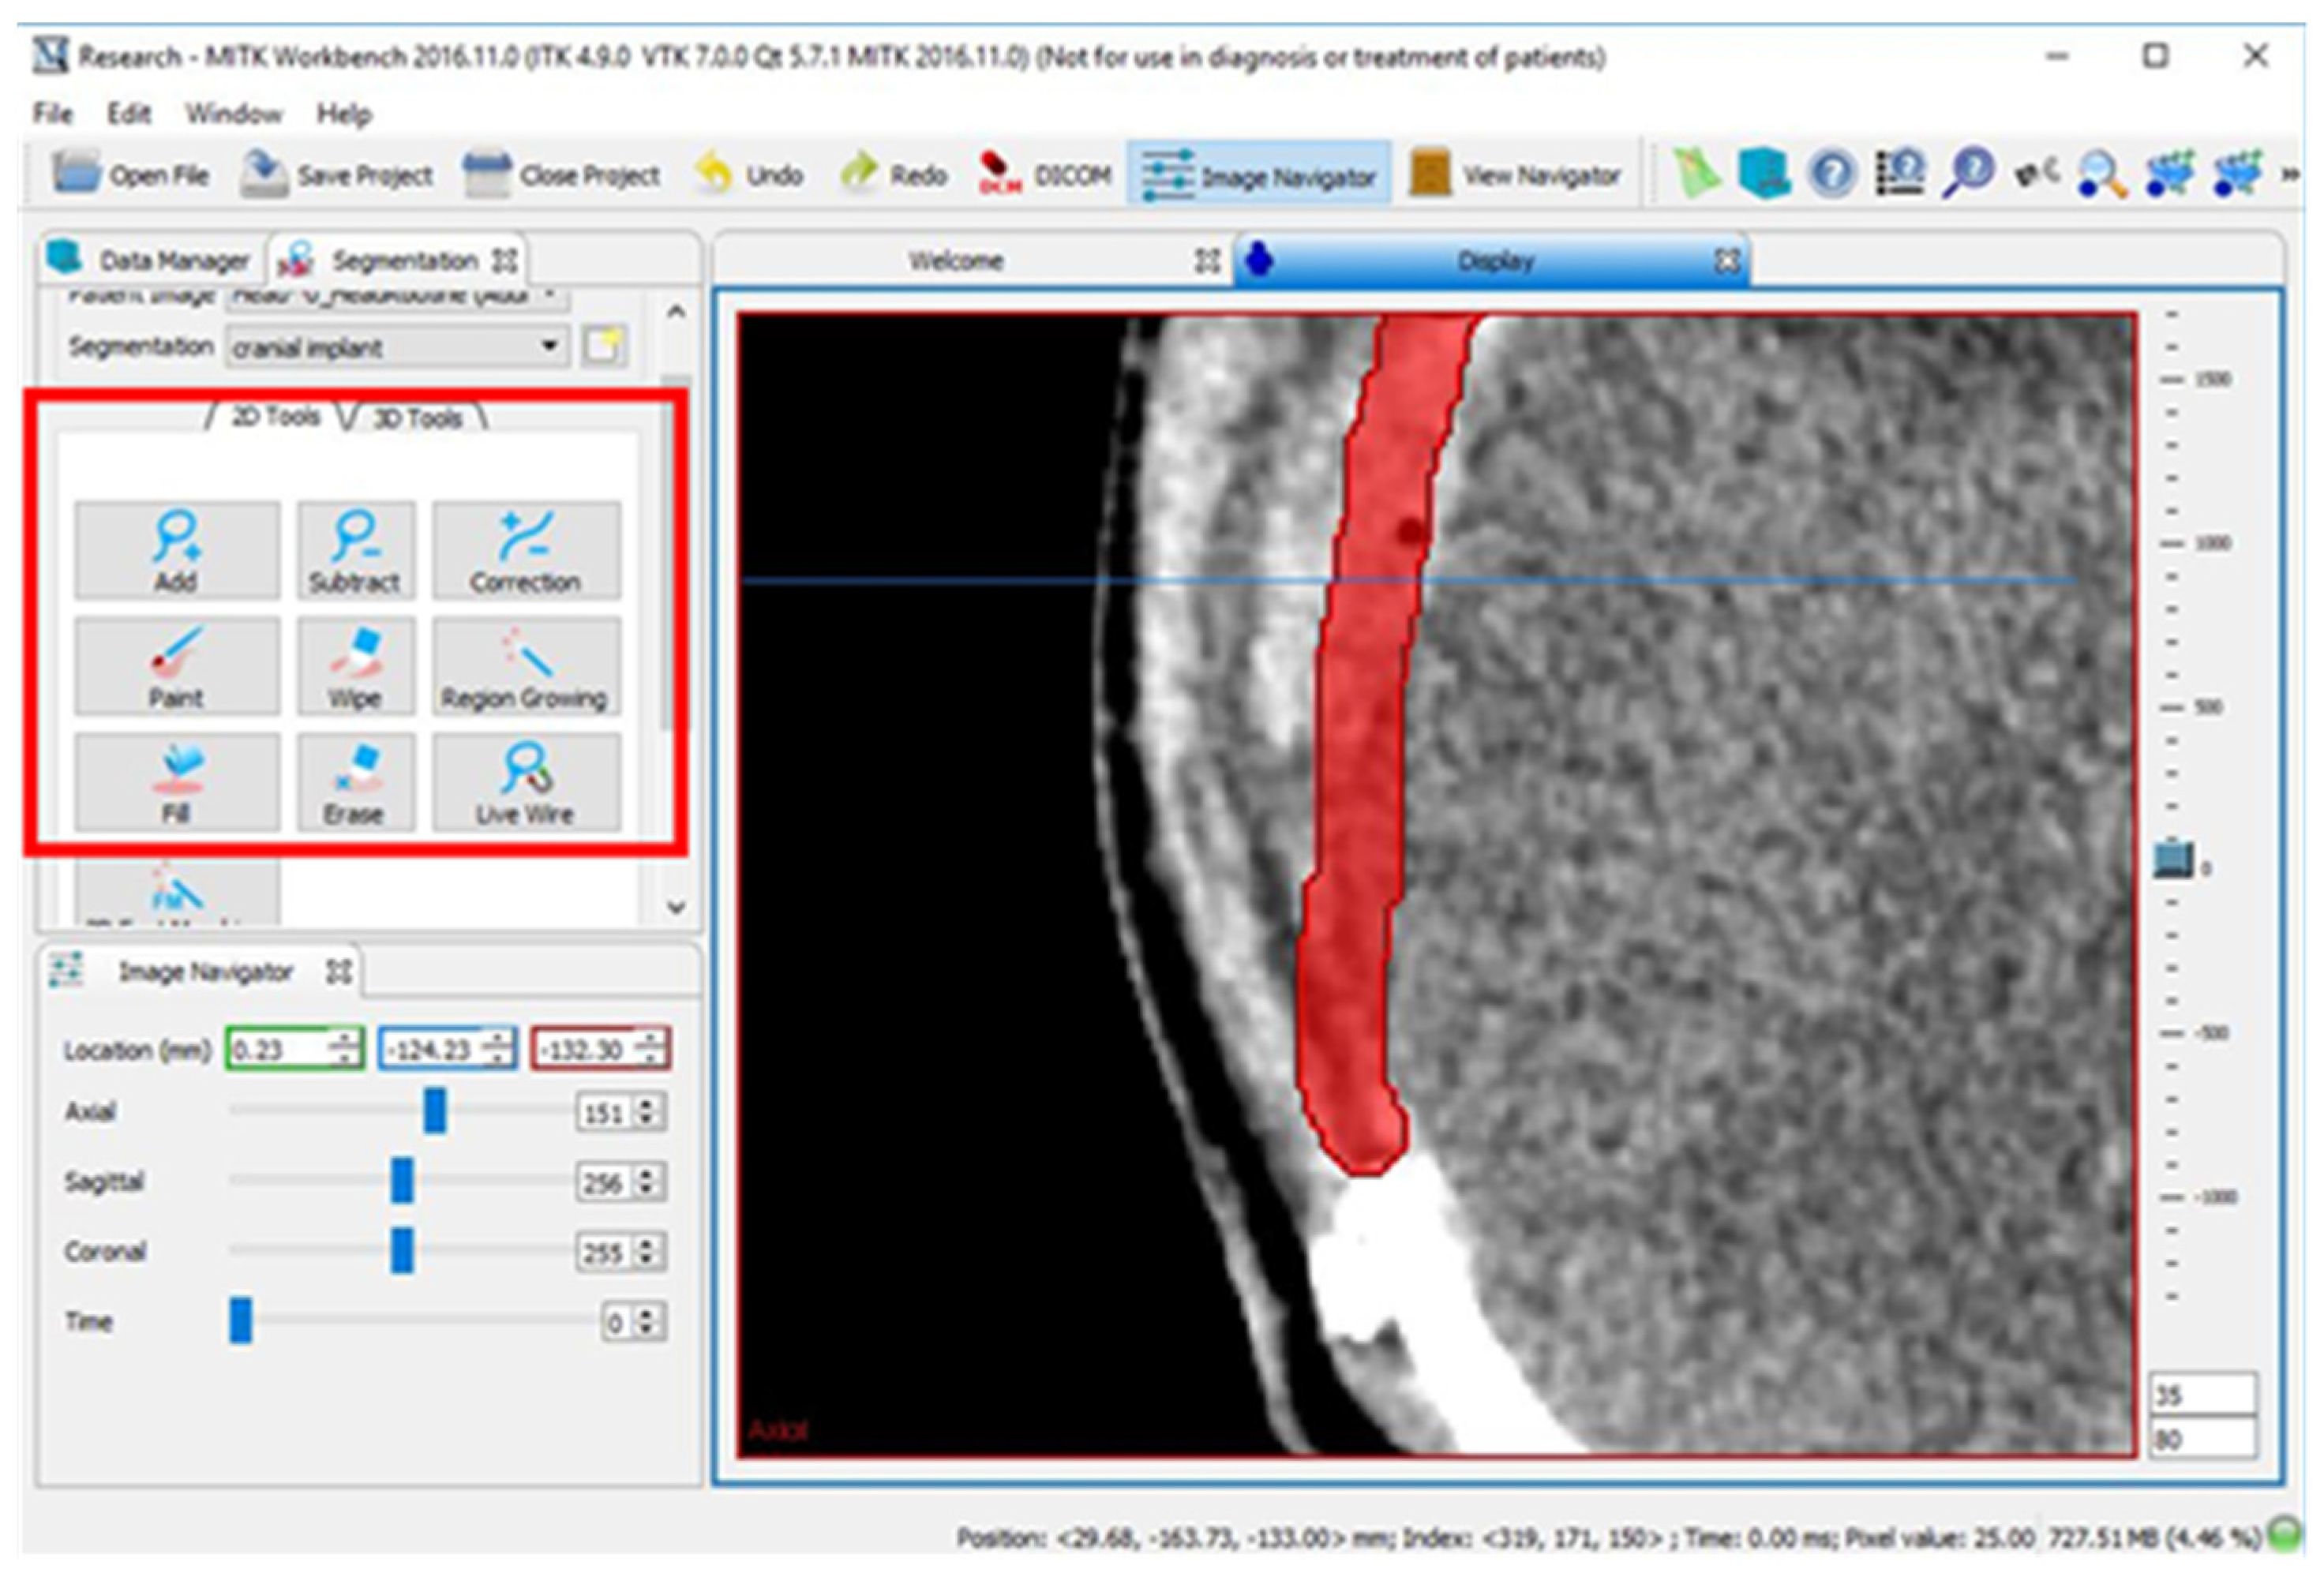

2.2. Design of Cranial Implants Using MITK Software